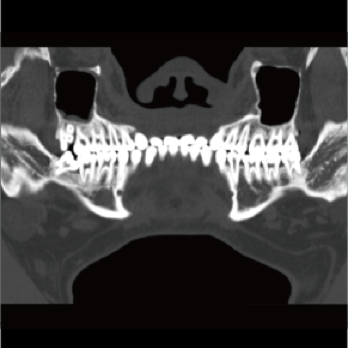

High-power generator delivers high mA output for rapid scanning of complex anatomy and large coverage areas, boosting scan speed while enhancing image signal-to-noise ratio and minimizing artifacts

Wide detector expands single-rotation coverage, shortens exam time, reduces motion artifacts, decreases radiation dose, and saves tube exposure time while effectively lowering operating costs